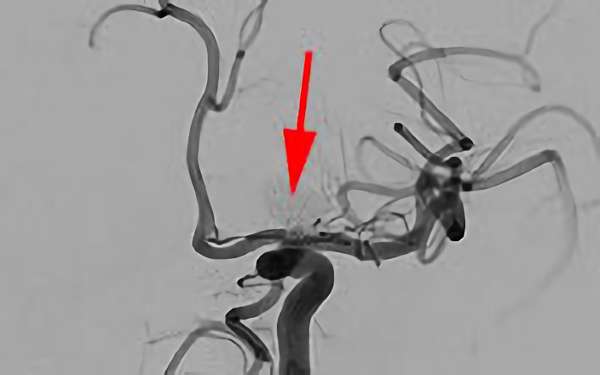

No.1600 手術前

No.1600 手術中

No.1600 手術後

くも膜下出血

脳底動脈瘤破裂

40代

救急外来